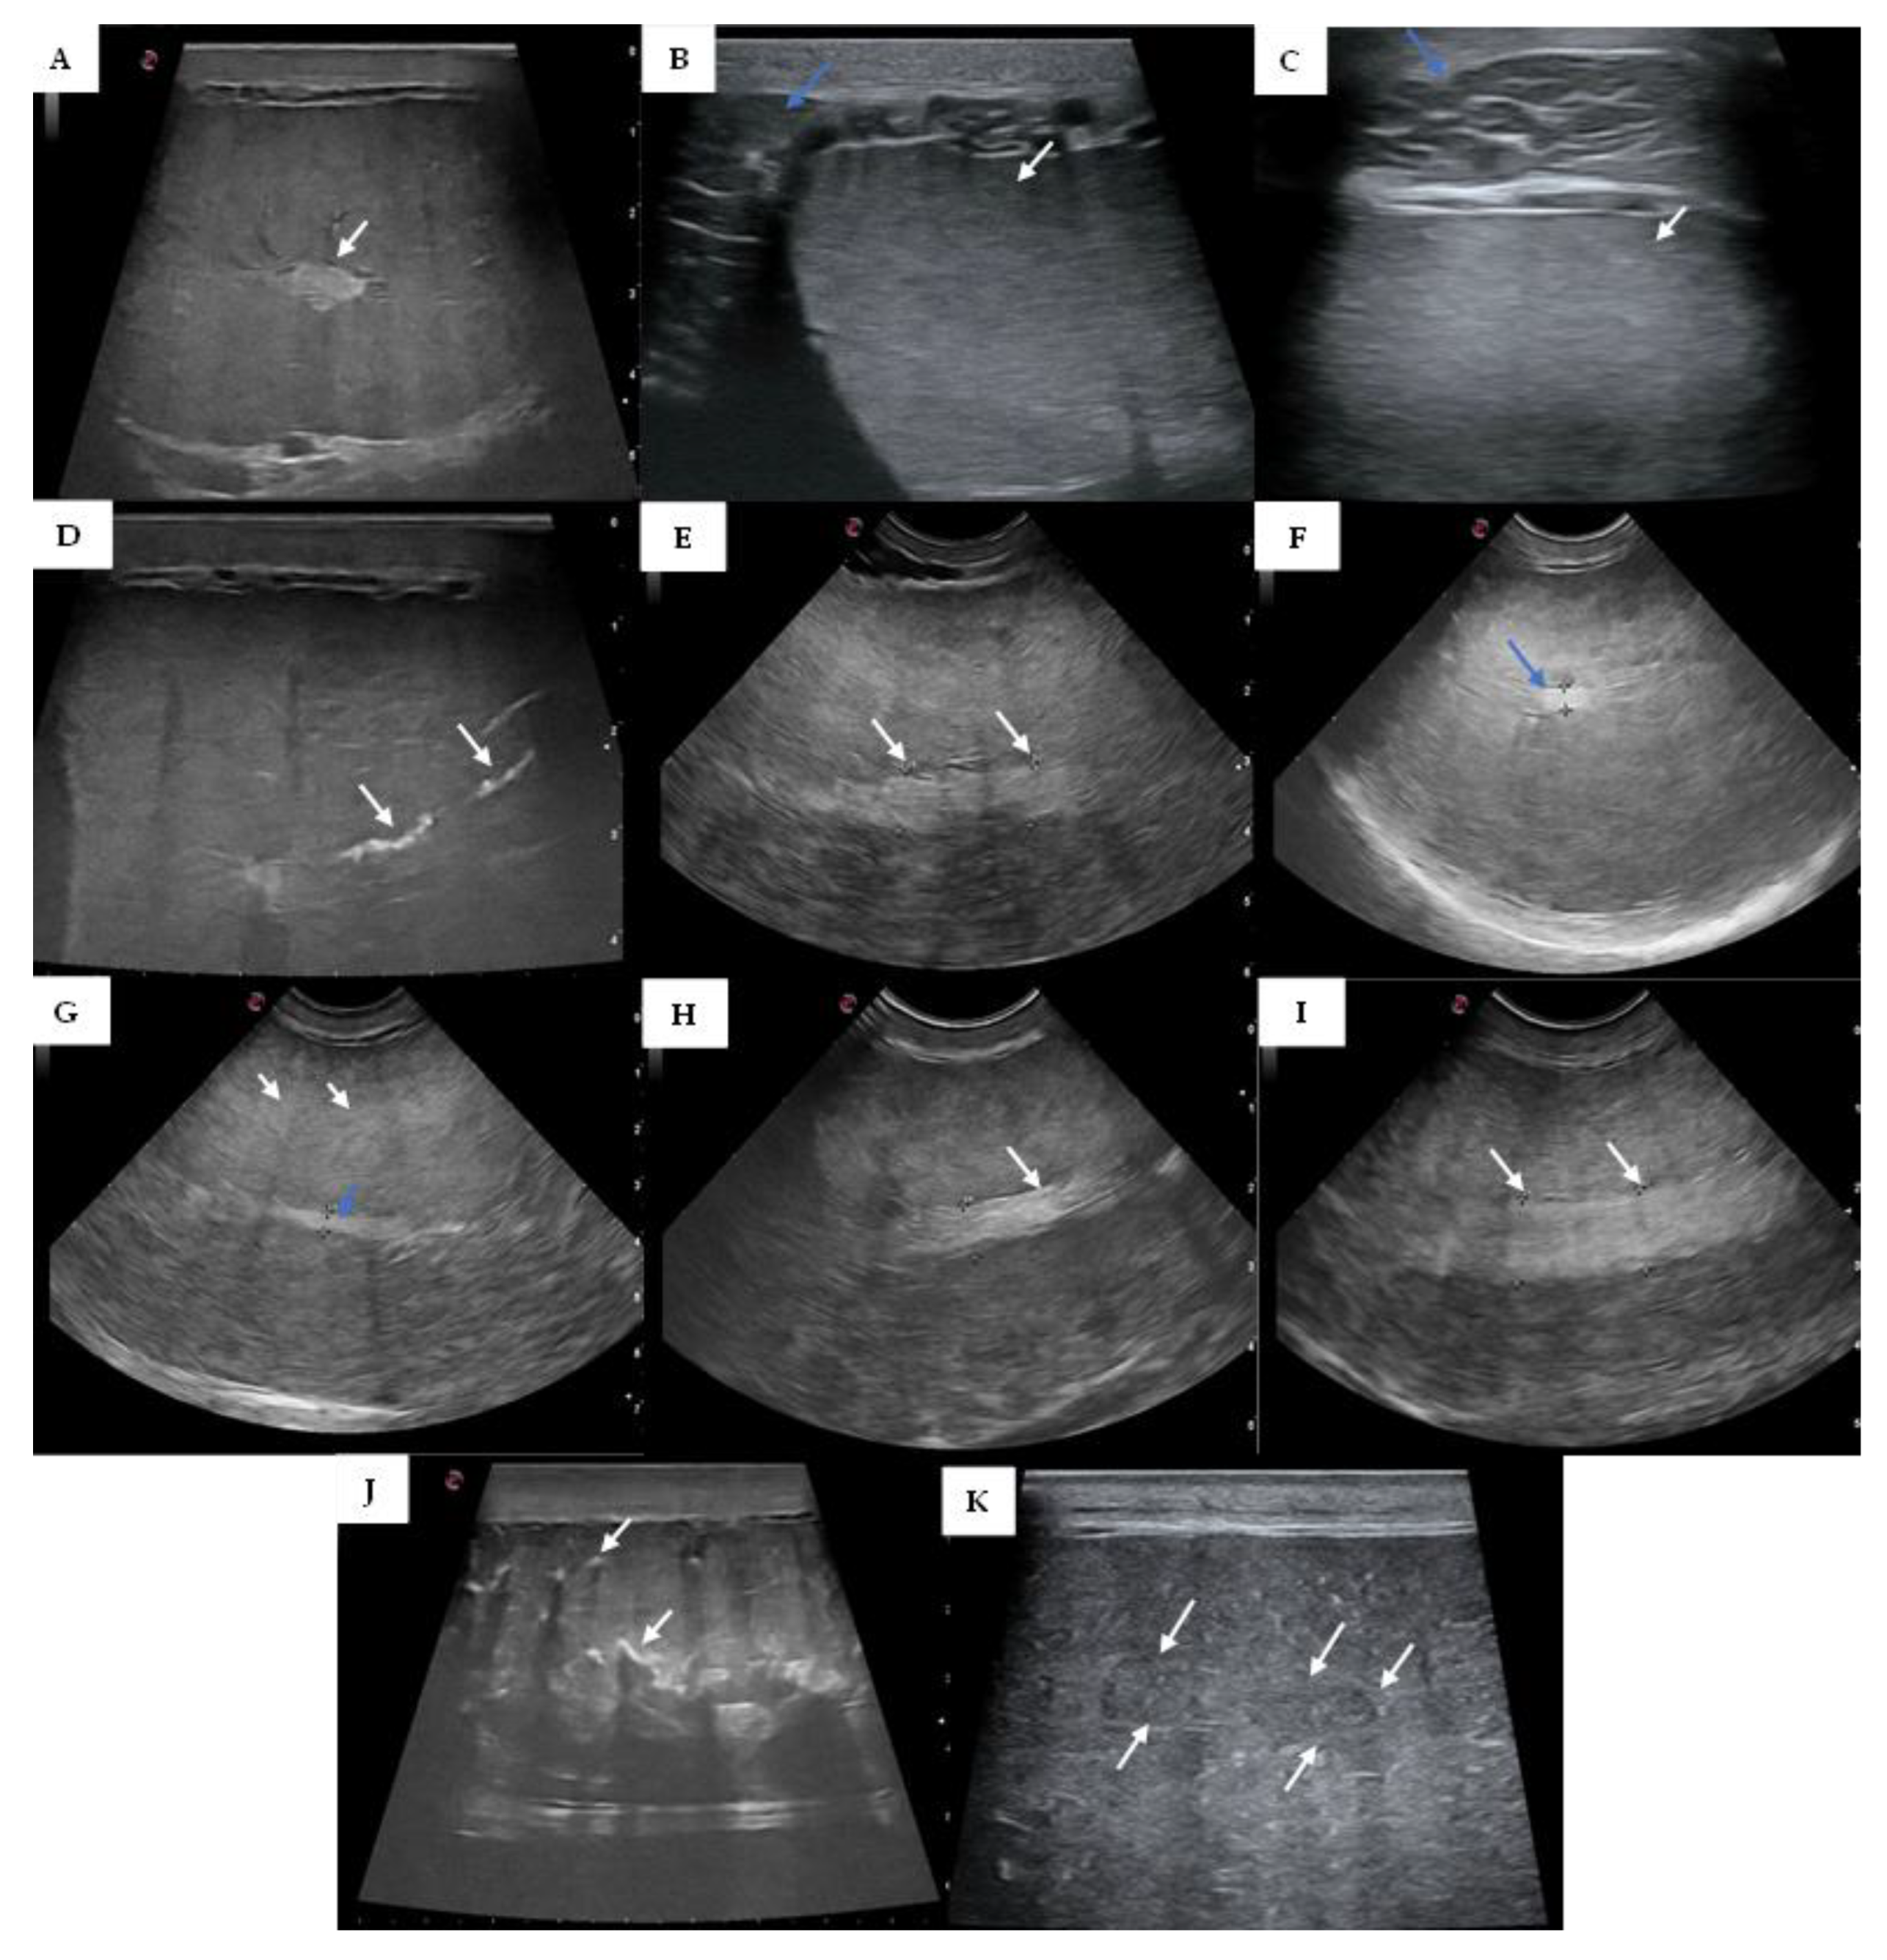

2.2. Testicular Ultrasonography

3.1. Testicular Ultrasonography